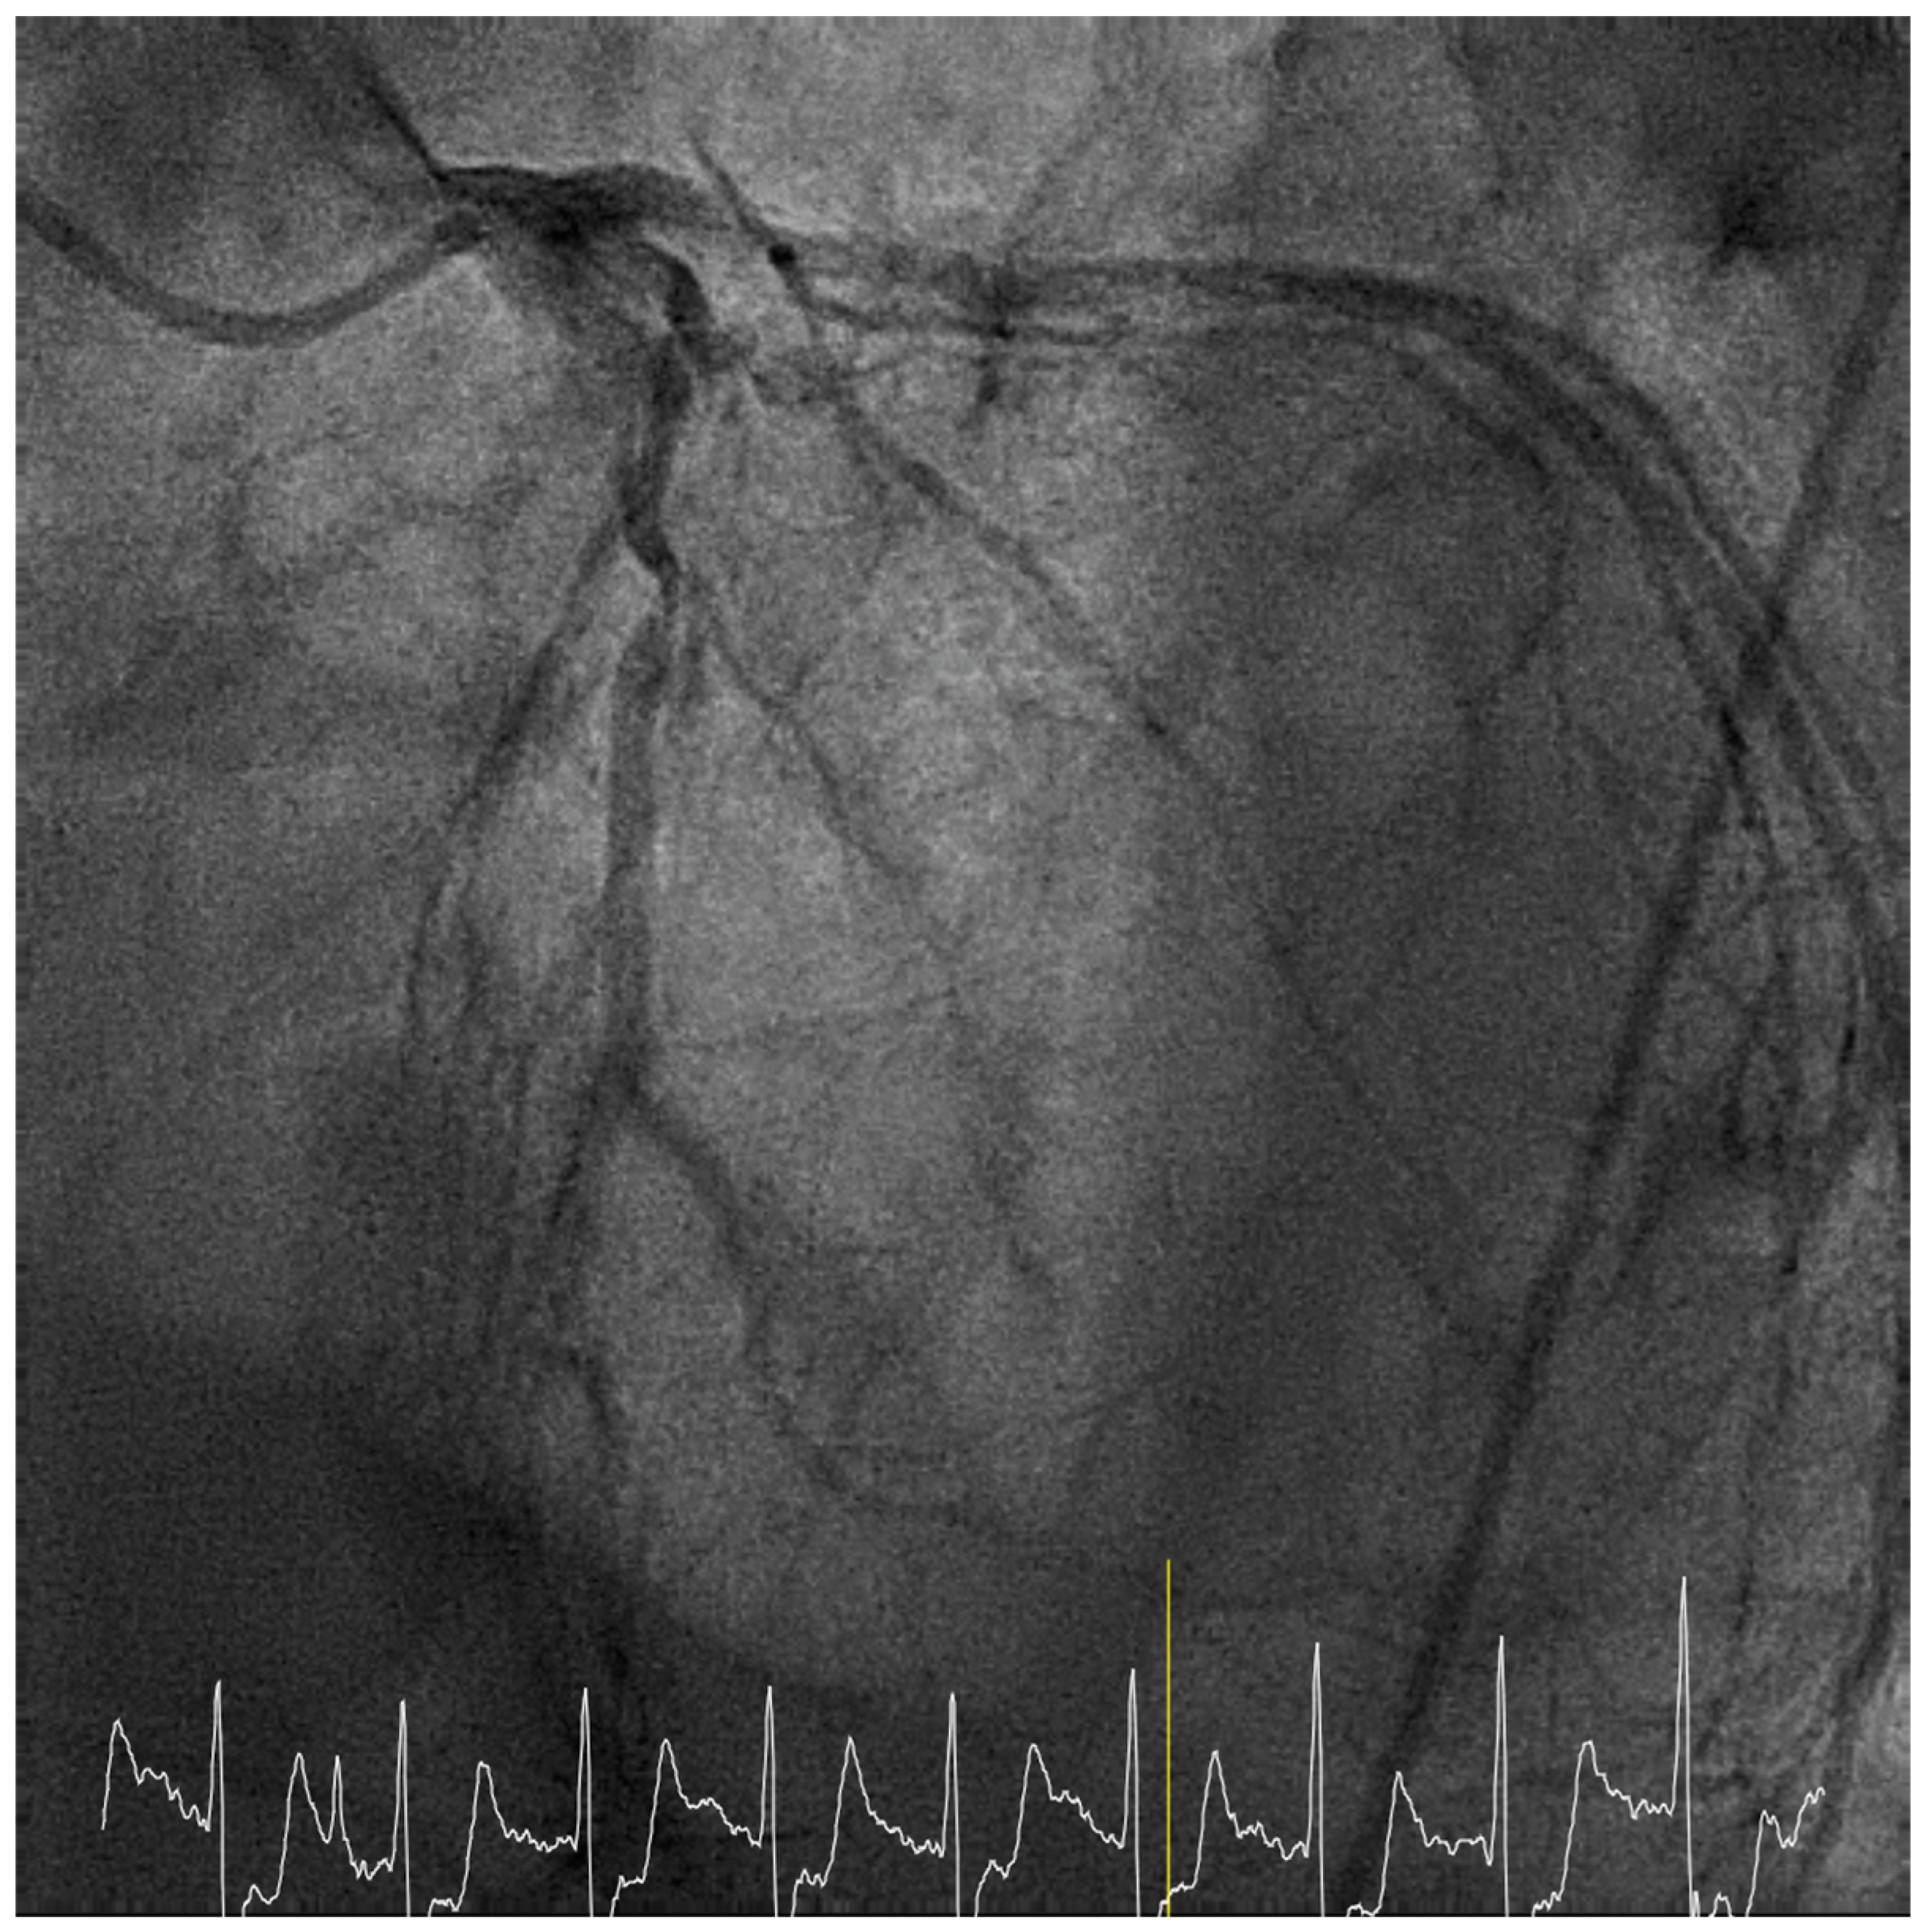

Case presentation

Solution